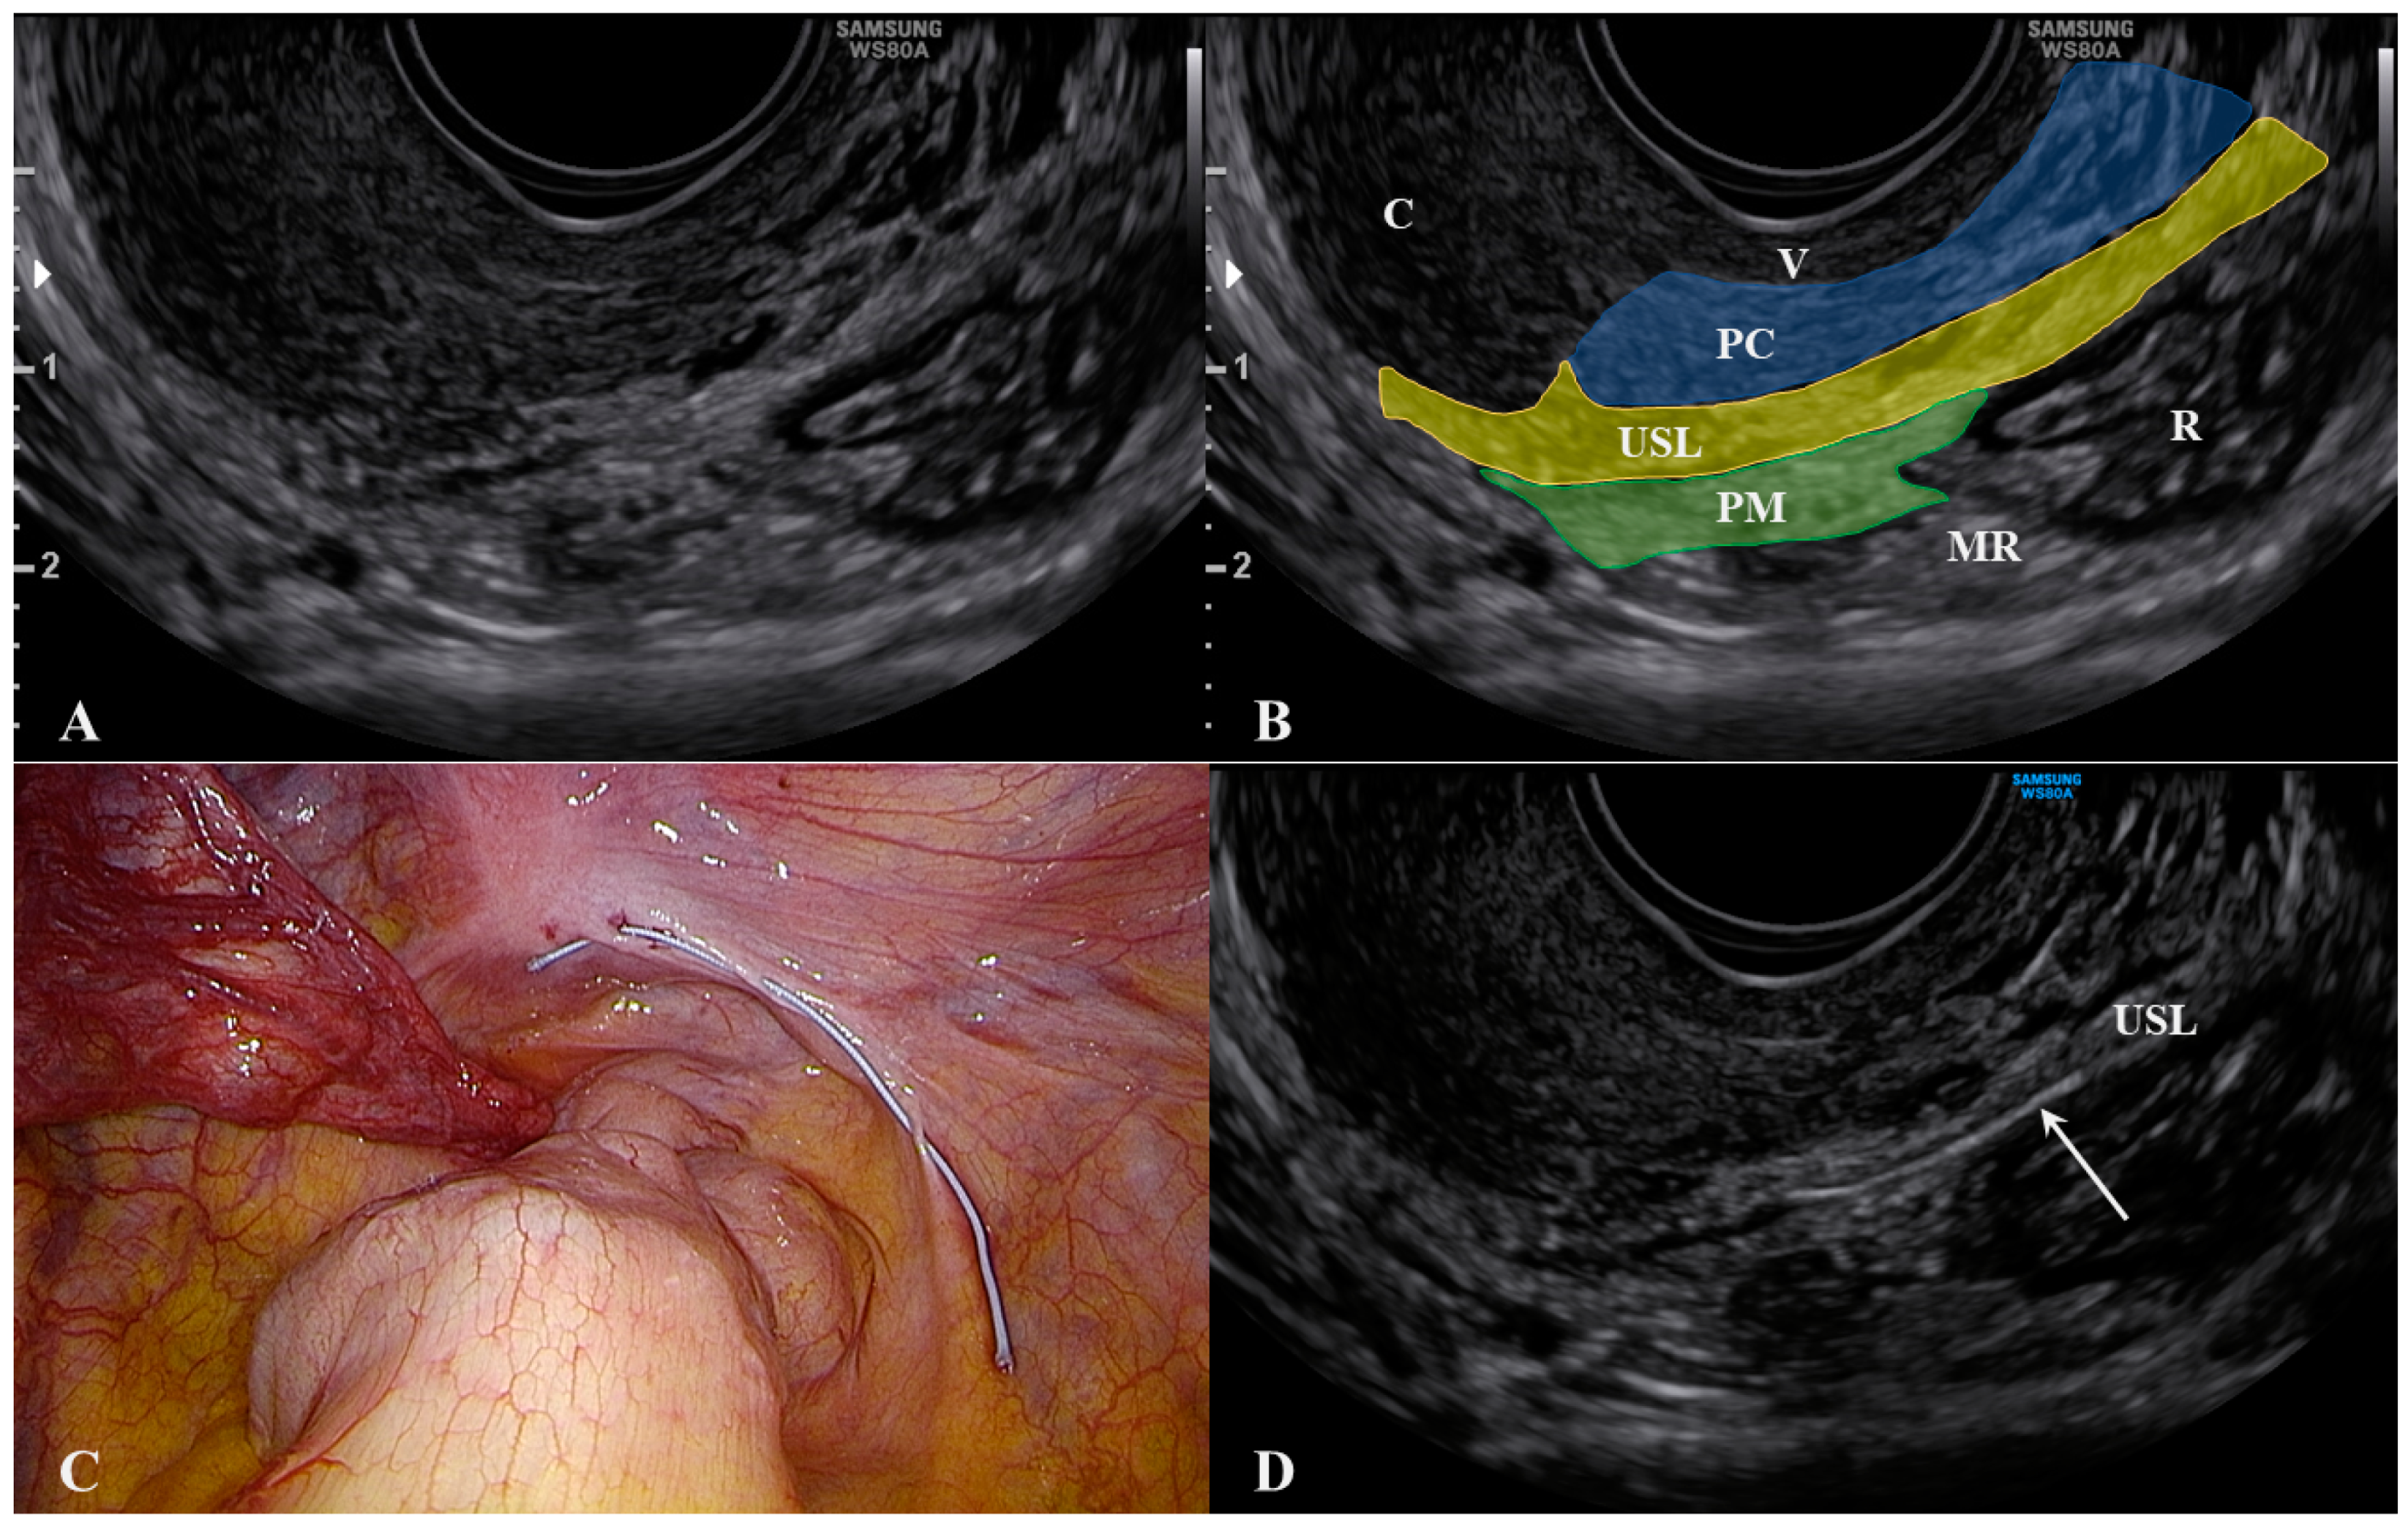

- Leonardi, M.; Martins, W.P.; Espada, M.; Arianayagam, M.; Condous, G. Proposed Technique to Visualize and Classify Uterosacral Ligament Deep Endometriosis with and without Infiltration into Parametrium or Torus Uterinus. Ultrasound Obstet. Gynecol. 2020, 55, 137–139. [Google Scholar] [CrossRef]